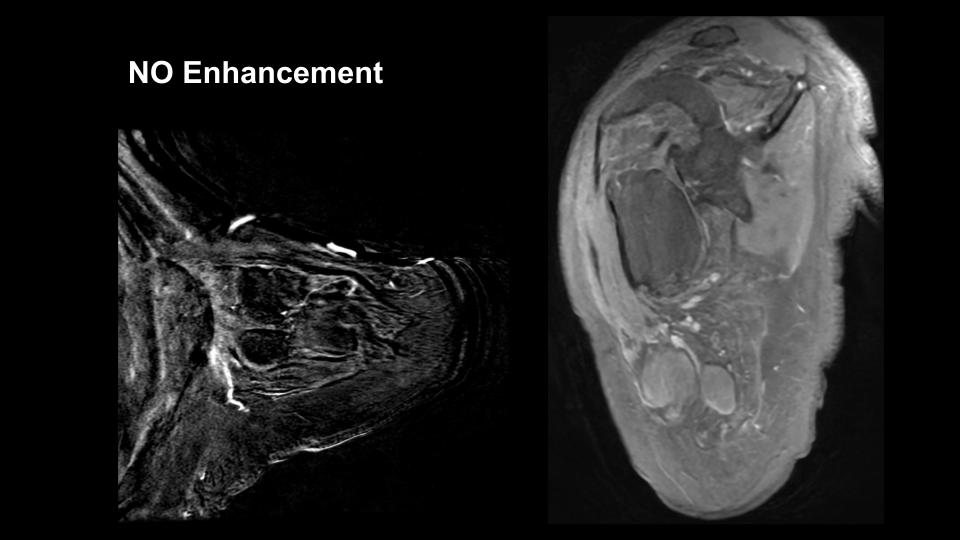

Figure 3 for case Stump neuromas

Figure 3

Discussion

Do not need to enhance

Diagnosis

Stump neuromas